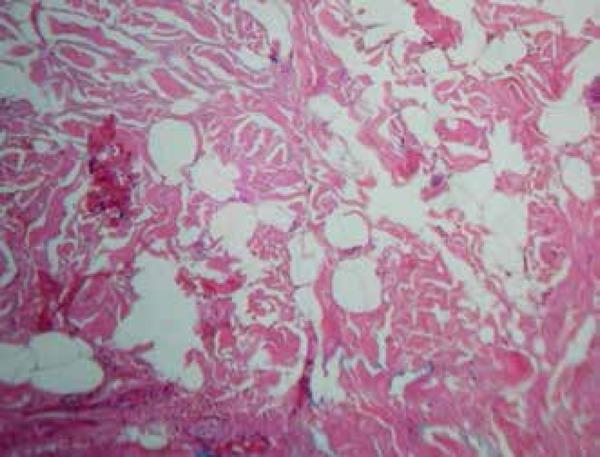

We report a case of nevus lipomatosus cutaneous superficialis of Hoffman-Zurhelle (NCLS), with multiple lesions, in a ten-year-old child. The NLCS is considered rare. The classical clinical presentation is characterized by multiple skin-colored or yellowish papules and nodules, which can have a linear distribution. Histologically, it is characterized by the presence of mature ectopic adipocytes in the dermis. The main therapeutic option is surgical excision. The classical Nevus lipomatosus cutaneous superficialis is reported in this case.

我们报告了一例10岁儿童的霍夫曼-祖尔赫尔浅表性皮肤脂肪瘤痣(NCLS),伴有多个皮损。NCLS被认为较为罕见。其典型临床表现为多个肤色或淡黄色丘疹及结节,可呈线状分布。组织学上,其特征为真皮内存在成熟的异位脂肪细胞。主要治疗选择是手术切除。本例报告了典型的浅表性皮肤脂肪瘤痣。